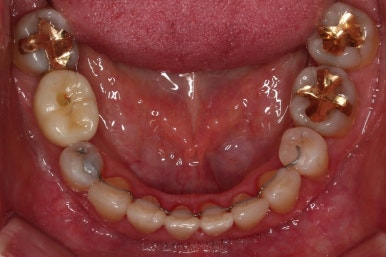

아랫니가 윗니보다 더 많이 삐뚤어 있는데요.

유치 잔존

말그대로 어릴 때 빠져야 할 유치가 남아있다는 뜻인데요.

앞니 사이에 뾰족하게 남아있다 보니 자리만 많이 차지하고 있는 모습이었고 다른 영구치를 더 삐뚤게 만들었어요.

딱히 영구치가 모자라진 않는데 유치가 잔존하는 굉장히 드물고 독특한 상황이었습니다.

적절한 시점에 유치를 뽑아내고 남은 공간을 줄여나갑니다.

아래쪽 임플란트는 움직이지 않기 때문에 해당 치아를 기준으로 다른 치아를 모두 셋팅해야 하는 매우 난이도 높은 치료가 진행되었습니다.